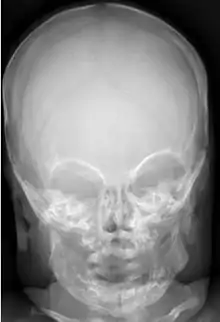

![]() МРТ пацієнта з доброякісною сімейною макроцефалією (чоловік з окружністю голови> 60 см) МРТ пацієнта з доброякісною сімейною макроцефалією (чоловік з окружністю голови> 60 см) | |

Доброякісна або сімейна макроцефалія

Доброякісна макроцефалія може виникати без причини або успадковуватися (при цьому вона вважається доброякісною сімейною макроцефалією і вважається мегаленцефальною формою макроцефалії). Діагноз сімейної макроцефалії визначається шляхом вимірювання окружності голови обох батьків та порівняння її з окружністю у дитини. Доброякісна та сімейна макроцефалія не пов'язані з неврологічними розладами[13], але нейророзвиток все одно оціненюється.